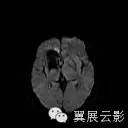

右侧基底节区可见不规则团片状混杂信号灶,累及右侧侧脑室前角,大小约15×34mm,边界尚清,呈爆米花样改变,T1WI等高信号,T2WI/FLAIR呈混杂稍高信号,边缘可见低信号环,无明显占位效应,DWI低信号。

海绵状血管瘤由扩张、衬有内皮的窦样间隙构成,窦样间隙排列紧密,无正常脑组织间隔,病变呈圆形或分叶状,几乎百分之百有瘤内出血。约80%发生于幕上,最常见于额、颞叶深部髓质区、皮髓质交界区和基底节区,也可发生于小脑、脑干和脊髓,约50%病例多发。CT平扫表现为一边缘清楚的圆形或类圆形高密度病灶,密度可均匀不一,常无灶周水肿,无或仅轻度占位征象。合并出血时,病灶可短时间内增大,出现明显占位征象,常伴钙化,增强扫描可有轻度至明显强化。MRI表现不一,取决于出血和时期,急性较大的出血可能掩盖海绵状血管瘤的典型特征,网状的“爆米花”样病变是最特征性的表现,中心呈混杂信号,周边有完整的含铁血黄素环。病灶内含有不同阶段的出血是信号不均匀的原因,在SWI中显示尤为清楚,常有多发低信号灶。